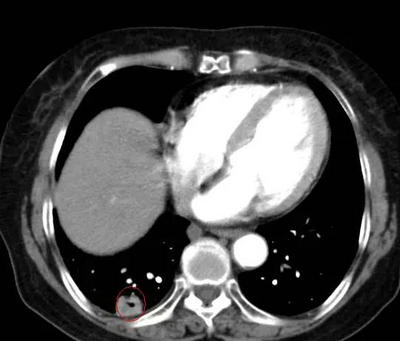

陶女士听到这样的解释非常满意立即让母亲接受了1疗程的治疗,患者的声嘶呛咳症状渐渐好转。为了寻找原发病灶的蛛丝马迹,丁主任让患者再次复查胸部增强CT,通过一帧帧仔细的分析影像资料,找到了一个小小的空洞病灶,通过与之前的影像资料对比,丁主任指出高度怀疑这个病灶有问题!马上请放射影像科吴峰医生为患者做CT引导下经肺穿刺检查(PTLB),病理结果是:中分化鳞状细胞癌。

原发病灶终于找到了!就是这个小小的空洞,曾经因为太小而被误诊为炎症空洞,每一个小小的忽视就有可能耽误患者的确诊和治疗,只有医生拥有较强的专业性和更多的耐心才能不放过任何隐匿的“敌人”。对于这个原发病灶,丁主任建议李奶奶再次进行伽玛刀治疗,以控制原发灶的发展,伽马射线犹如外科手术般精确对肿瘤细胞进行进行摧毁。

▲ 上图为曾被误诊为炎症的薄壁空洞,下图为增厚的空洞病灶,经穿刺后确诊为肺鳞癌的原发病灶